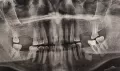

Добрый день! Заболел зуб. Обратилась в частную стоматологию. Нашли периодонтит. Почистили зубные каналы. Удалили нерв (при этом зуб остается чувствительный). Сделала снимок. На снимке видна белая штука. Что ожидает зуб в дальнейшем?

Добрый день, уважаемая Лидия. При первичном приеме доктор должен депульпировать каналы и установить в них лекарство (белое вещество). Затем, в следующее посещение, доктор запломбирует канал, а еще на следующее установит постоянную пломбу. При этом легкое недомогание возможно, зуб может реагировать при накусывании. Лечение периодонтита происходит в три приема (как минимум). Выполняйте рекомендации.